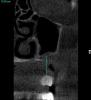

SergeyAL Опубликовано 29 мая, 2013 Поделиться Опубликовано 29 мая, 2013 коллеги столкнулся с такой ситуацией 5 лет назад были установлены поднадкостничные имплантаты имени д-ра Раада пациенту пообещали, что 5 лет они точно прослужат на срезах КТ видно, что прослужили, но в некоторых местах албвеолярного отростка не осталось после их службы)) послу удаления их остались сплошные рубцы, удалять которые смысла не импло, т.к. они были спаяны со Шнайдеровой мембраной или то, что от нее осталось последние фотографии через 4 месяца после их удаления, слизистая представляет собой сплошной рубец. коллеги, поделитесь, какую тактику применяете при выраженных рубцовых деформациях, когда впереди еще костная пластика, имплантация и т.д. Ссылка на комментарий

SergeyAL Опубликовано 30 мая, 2013 Автор Поделиться Опубликовано 30 мая, 2013 коллега, каких синусов, толщина в области синуса менее 3-х мм, а расстояние от костной ткани до предполагаемой реставрации 10-15мм!!!!! Ссылка на комментарий

SergeyAL Опубликовано 30 мая, 2013 Автор Поделиться Опубликовано 30 мая, 2013 там выраженная редукция тканей по ширине,даже в в области синуса около 3 мм Ссылка на комментарий

SergeyAL Опубликовано 30 мая, 2013 Автор Поделиться Опубликовано 30 мая, 2013 там не везде есть костная пластинка, местами рубцы из ротовой полости спаяны со Шнайдеровой мембраной или что там от нее осталось Ссылка на комментарий